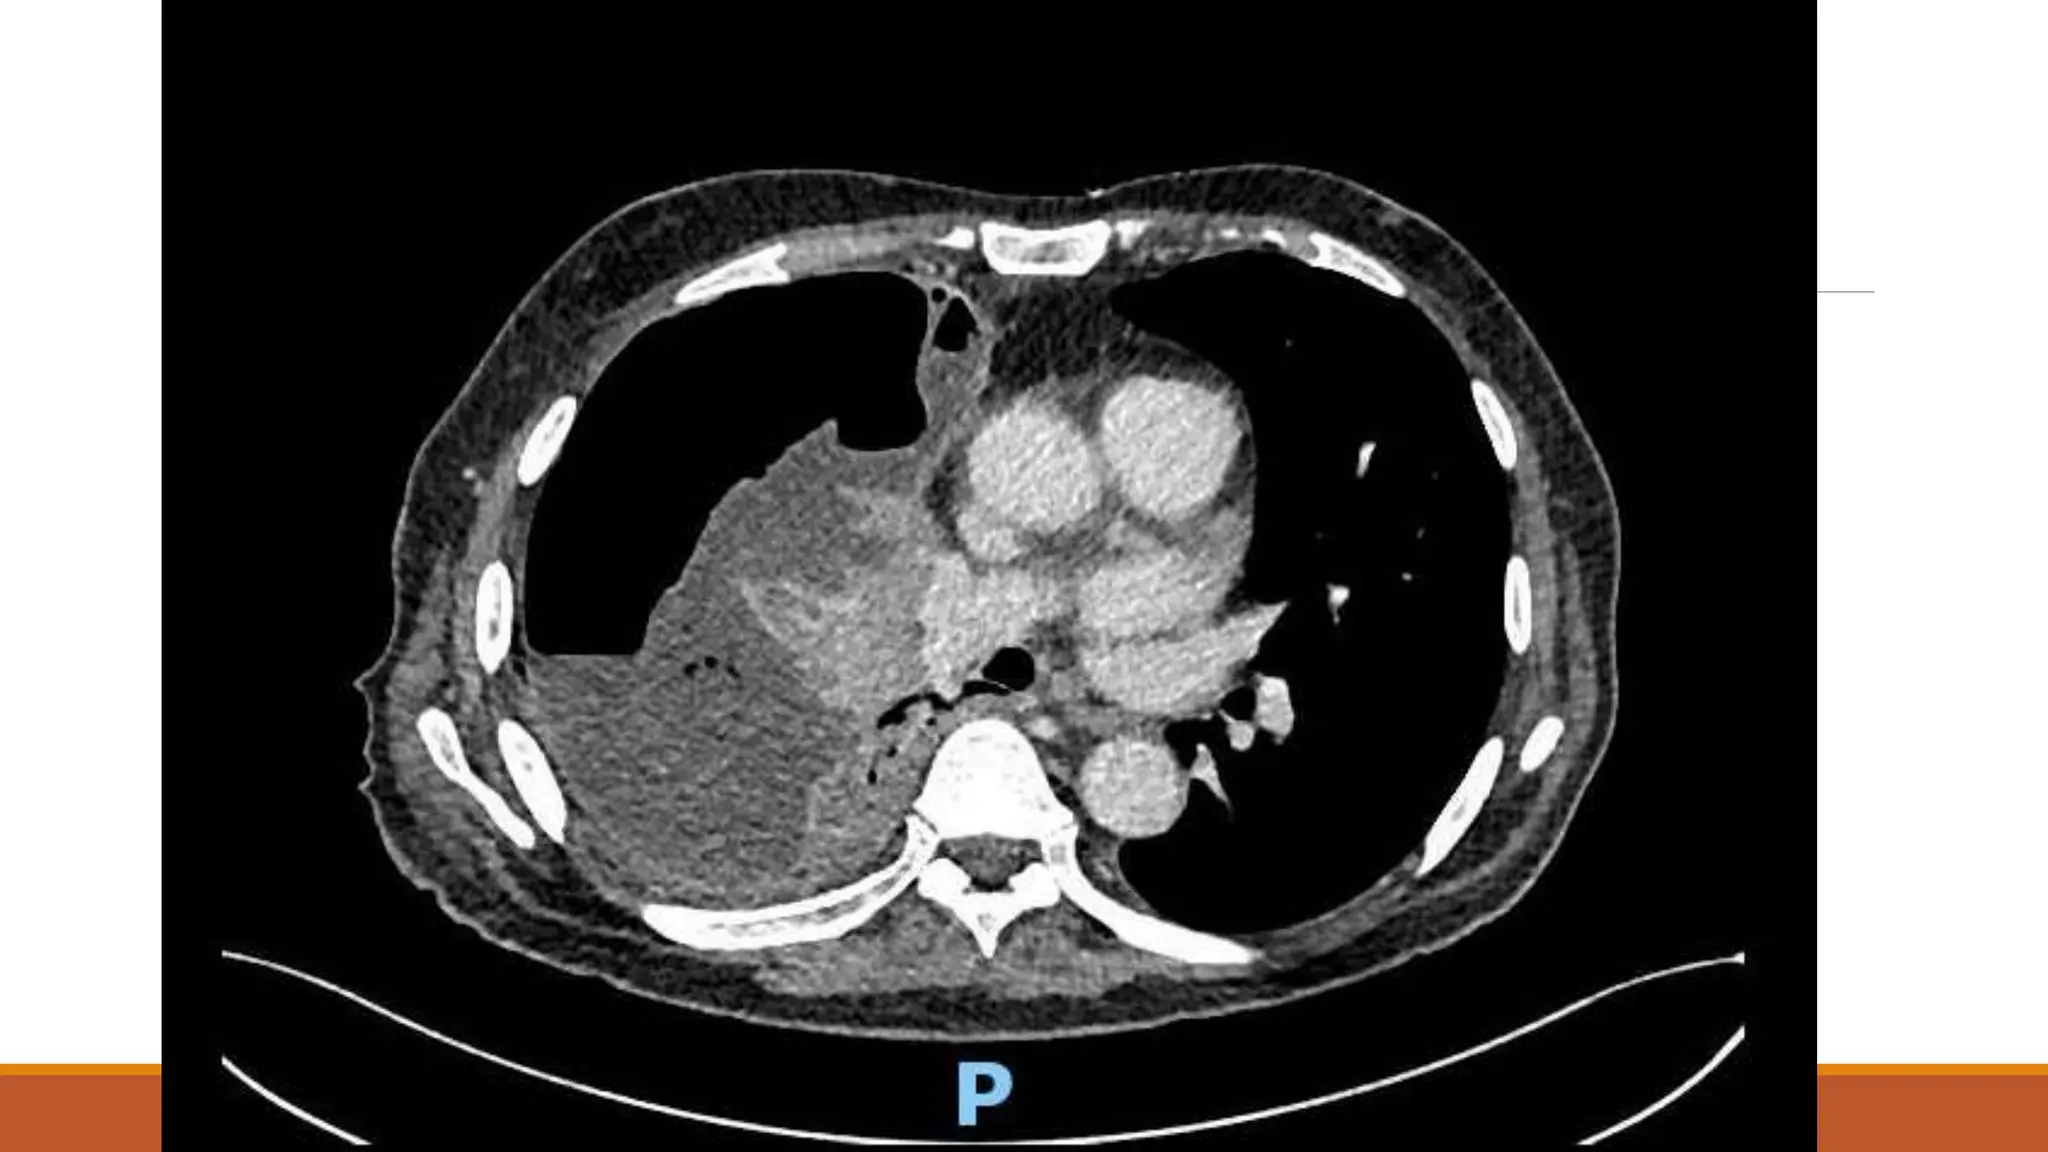

63 male

Normally F&W, no regular medications

Became unwell 7th Dec 2020 – cough, yellow sputum

Saw GP 23rd Dec – oral doxy

No real improvement – Clarithromycin 6/1/21

Again no improvement

Progressive loss of appetite and weight over a couple of months – given fortisip, which stopped

weight loss, but poor appetite continued

Progressive right shoulder pain and inability to lie on left side due to dyspnoea

On examination

OE: Acutely distressed, in significant pain and sats dropped to 80% when sat forwards, but 98%

when reclined at 60 degrees

Chest – no air entry right side

Fluid LDH >50000

Results Fluid LDH >50000 pHunable due to viscosity Protein 63 Glucose <0.6 Fluid grew Streptococcus anginosus